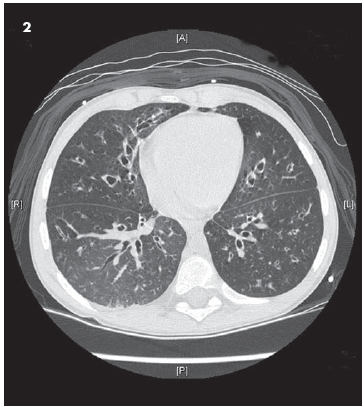

A chest CT scan obtained several weeks later (Figure 2) demonstrates in more detail the bronchiectasis and hyperinflation seen on the radiographs. Note the thickened walls of the airways, which can also be appreciated on the lateral view of the initial radiographs. Look for the fuzzy "cheerios," which represent the airways seen end-on, with thickened/inflamed walls.